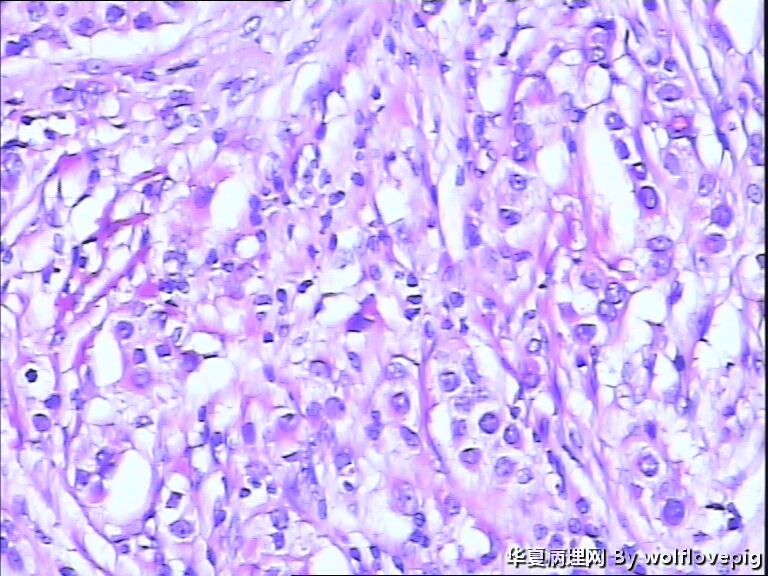

B3937求助!乳腺包块。

女,60y,发现右乳包块6+月。

灰白不整形组织一块:3*2*1.5cm,切面有一灰白区域,边界欠清,质韧。

• 求助!乳腺包块。图1

图1

• 求助!乳腺包块。图2

图2

• 求助!乳腺包块。图3

图3

• 求助!乳腺包块。图4

图4

标签:乳腺浸润性癌

浸润性癌。

浸润性导管癌,最好标记肌上皮。

浸润性导管癌

浸润性导管癌,分化差,除外混合癌(导管癌+小叶癌),免疫组化证实。(本例图像很多,局部炎症反应重,瘤细胞还成合体样无腺管形成似髓样癌,局部似炎性乳癌,局部似小叶癌,呵呵)